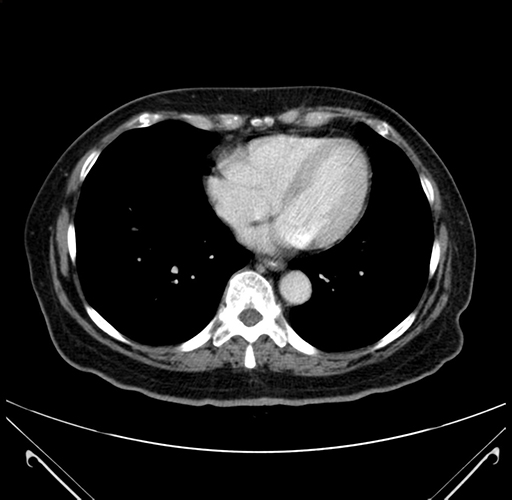

Axial Venous

Based on your CT findings, which issue(s) would give reason for "planned slowing down moment(s)" in this case?

Considering a standard right hepatectomy procedure, what step(s) of the operation would you do differently in this case?